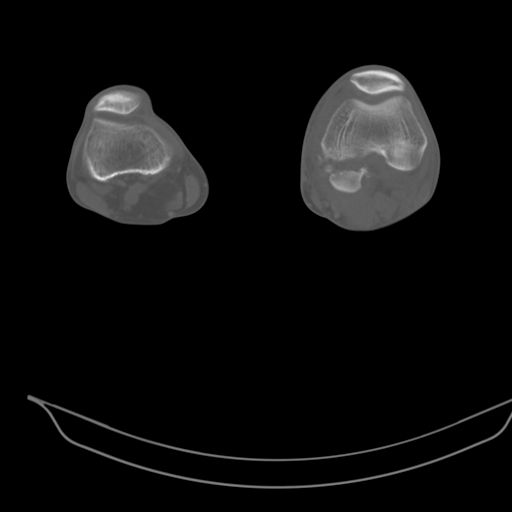

При внутрисуcтавных переломах трехмерные (3D) изображения, кроме красивого снимка, не дают полную информацию о состоянии отломков, самыми информативными являются корональные срезы на КТ и обычная длинная ренгенограмма конечности для сравнения оси конечности.

Фронтальные внутрисуставные переломы мыщельков бедра, так называемые Hoffa fracture, не частые, но встречающиеся переломы, в основном они связаны с травмой высокой энергией.

В зависимости от смещения рекомендуется сопоставление костных фрагментов с последующей жесткой фиксацией.

В вашем случае доступ будет медиальный, сопоставить развернутый медиальный мыщелок и фиксацию надо произвести в передне-заднем

направлении шурупами 4.5 мм в диаметре, углубив головку шурупов под хрящ, а поперечную фиксацию - межмыщелковыми шурупами. Желательно применить шурупы 6.3 мм в диаметре. Дополнительная Buttress technique пластина предотвратит перелом от скольжения.